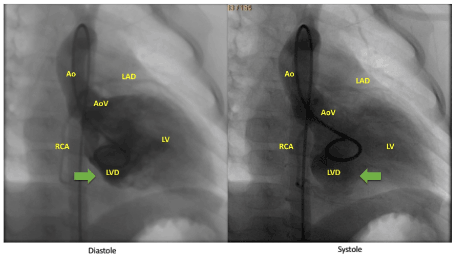

We present a 2 year 8 months old girl, 13.4 kg of weight, who was referred for a second opinion with the diagnosis of heart tumor and a complex ventricular arrhythmia. She had a history of two episodes of loss of consciousness. The second one was witnessed by a paramedic who noted an irregular heart rhythm at the time of the event. The electrocardiogram (ECG) showed sinus rhythm, normal axis, multiple ventricular extrasystoles (VEs) with a morphology of the right bundle branch block (RBBB) and a left axis deviation as well as 1 triplet of VE 100/min (Figure 1). In the Holter ECG examination, which was performed on two antiarrhythmic drugs (amiodarone 70 mg, mexiletine 180 mg/24h), we noted 38691 VEs (32% of all QRS), 1724 non-sustained ventricular tachycardia (nsVT) (up to 10 subsequent beats and maximal heart rate 205/min) (Figure 2). Moreover, constant ECG monitoring revealed sustained ventricular tachycardia with maximal heart rhythm 280/min followed by a spontaneous return of sinus rhythm (Figure 3). TTE revealed a large contractile pouch with a broad connection to the ventricle close to the mitral valve (MV) ring. The contractility of the outpouching area was asynchronous (Figures 4 and 5). Cardiac catheterization procedure confirmed the diagnosis and revealed the LVD surrounding the MV (Figure 6).

Figure 6. Cardiac catheterization procedure – LVD surrounding the MV. Asynchronous contraction of the LVD. Ao – aorta; AoV – aortic valve; LAD – left anterior descending artery; LV - left ventricle; LVD - left ventricle diverticulum; RCA – right coronary artery